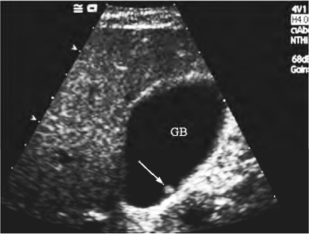

1.胆囊壁上附着单个或多个圆形或半圆形的团块,有时有蒂相连,位置不随体位改变而移动(图25-9)。

图25-9 胆囊息肉(箭头所示)声像图